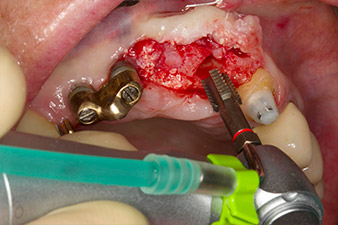

Une fois la cicatrisation primaire obtenue, les tissus mous ont été formés à l'aide du bridge doublé à la base. Deux mois plus tard, la zone a été exposée au moyen d'une incision de la crête alvéolaire légèrement orientée côté palatin (Fig 2). Les dimensions de l'os alvéolaire se sont avérées suffisantes en position 22. Les Figures 2 et 4 illustrent la préparation du lit implantaire, le taraudage et la pose de l'implant à l'aide de l'Implantmed.

le forage pilote est effectué avec le nouvel Implantmed et le contre-angle WS-56 L

Fig. 2 : Deux mois plus tard, le forage pilote est effectué avec le nouvel Implantmed et le contre-angle WS-56 L (programme P1, ratio 1:1). Le refroidissement est effectué au moyen de la buse de pulvérisation située à gauche (pour les utilisateurs droitiers).